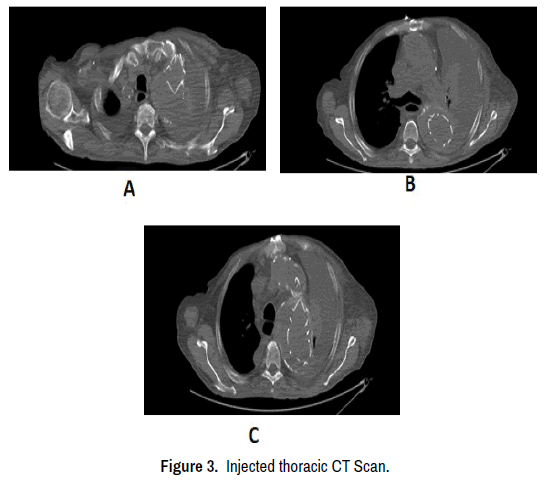

A CXR performed on the 16th of April showed a complete left pleural effusion as shown in Figure 2. An injected thoracic CT Scan was then required to elucidate the origin of the pleural effusion, the CT scan is shown in Figure 3.

Figure 3. Injected thoracic CT Scan.

On the Scan report, the imagery shows the presence of several periprosthetic leak sites; the first of type I is located postero-superiorly at the level of the arch of the aorta starting a few centimeters from the ostium of the left sub clavicular artery, a second of type III located on the anterior wall of the descending aorta and a third probably independent of the previous one but of the same type, lower located at the level of the descending aorta near a prosthetic plicature at this level.